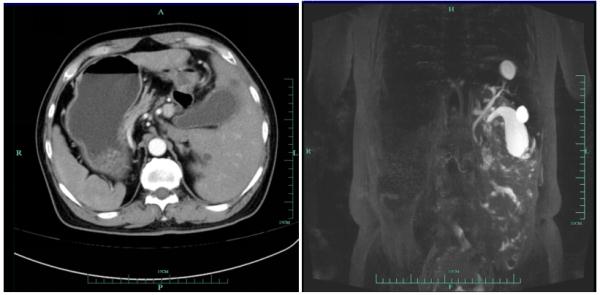

杭州市第一人民醫院最近來了一位罕見的“鏡面人”——68歲的高大伯(化名),內臟器官全部“逆生長”:心臟、脾臟長在右邊,肝臟和膽囊長在了左邊,就好比是正常人在鏡子裡看到的自己。

來到市一醫院肝膽胰外科病房,一系列檢查後發現高大伯的膽囊炎非同小可,膽囊壁異常厚,整個膽囊有14.5公分大。血常規檢查結果顯示:高大伯白細胞增高,超敏CRP有265!“情況比較嚴重,必須馬上做手術”接診的市一醫院肝膽胰外科殷俊傑主治醫師當機立斷。

腹腔鏡下,殷醫生髮現高大伯的膽囊炎比想象中的還重,一塊石頭卡在膽囊頸,膽汁出不去後,整個膽囊已經壞疽,再晚一些就會面臨穿孔的危險。這樣的手術,即使是正常情況下也屬於比較棘手的。高大伯的膽囊已經部分和肝臟粘連,留給醫生手術的空間幾乎沒有。此外,由於炎症嚴重,時刻面臨出血的問題。要在罕見的“鏡面人”身上做,更是難上加難。